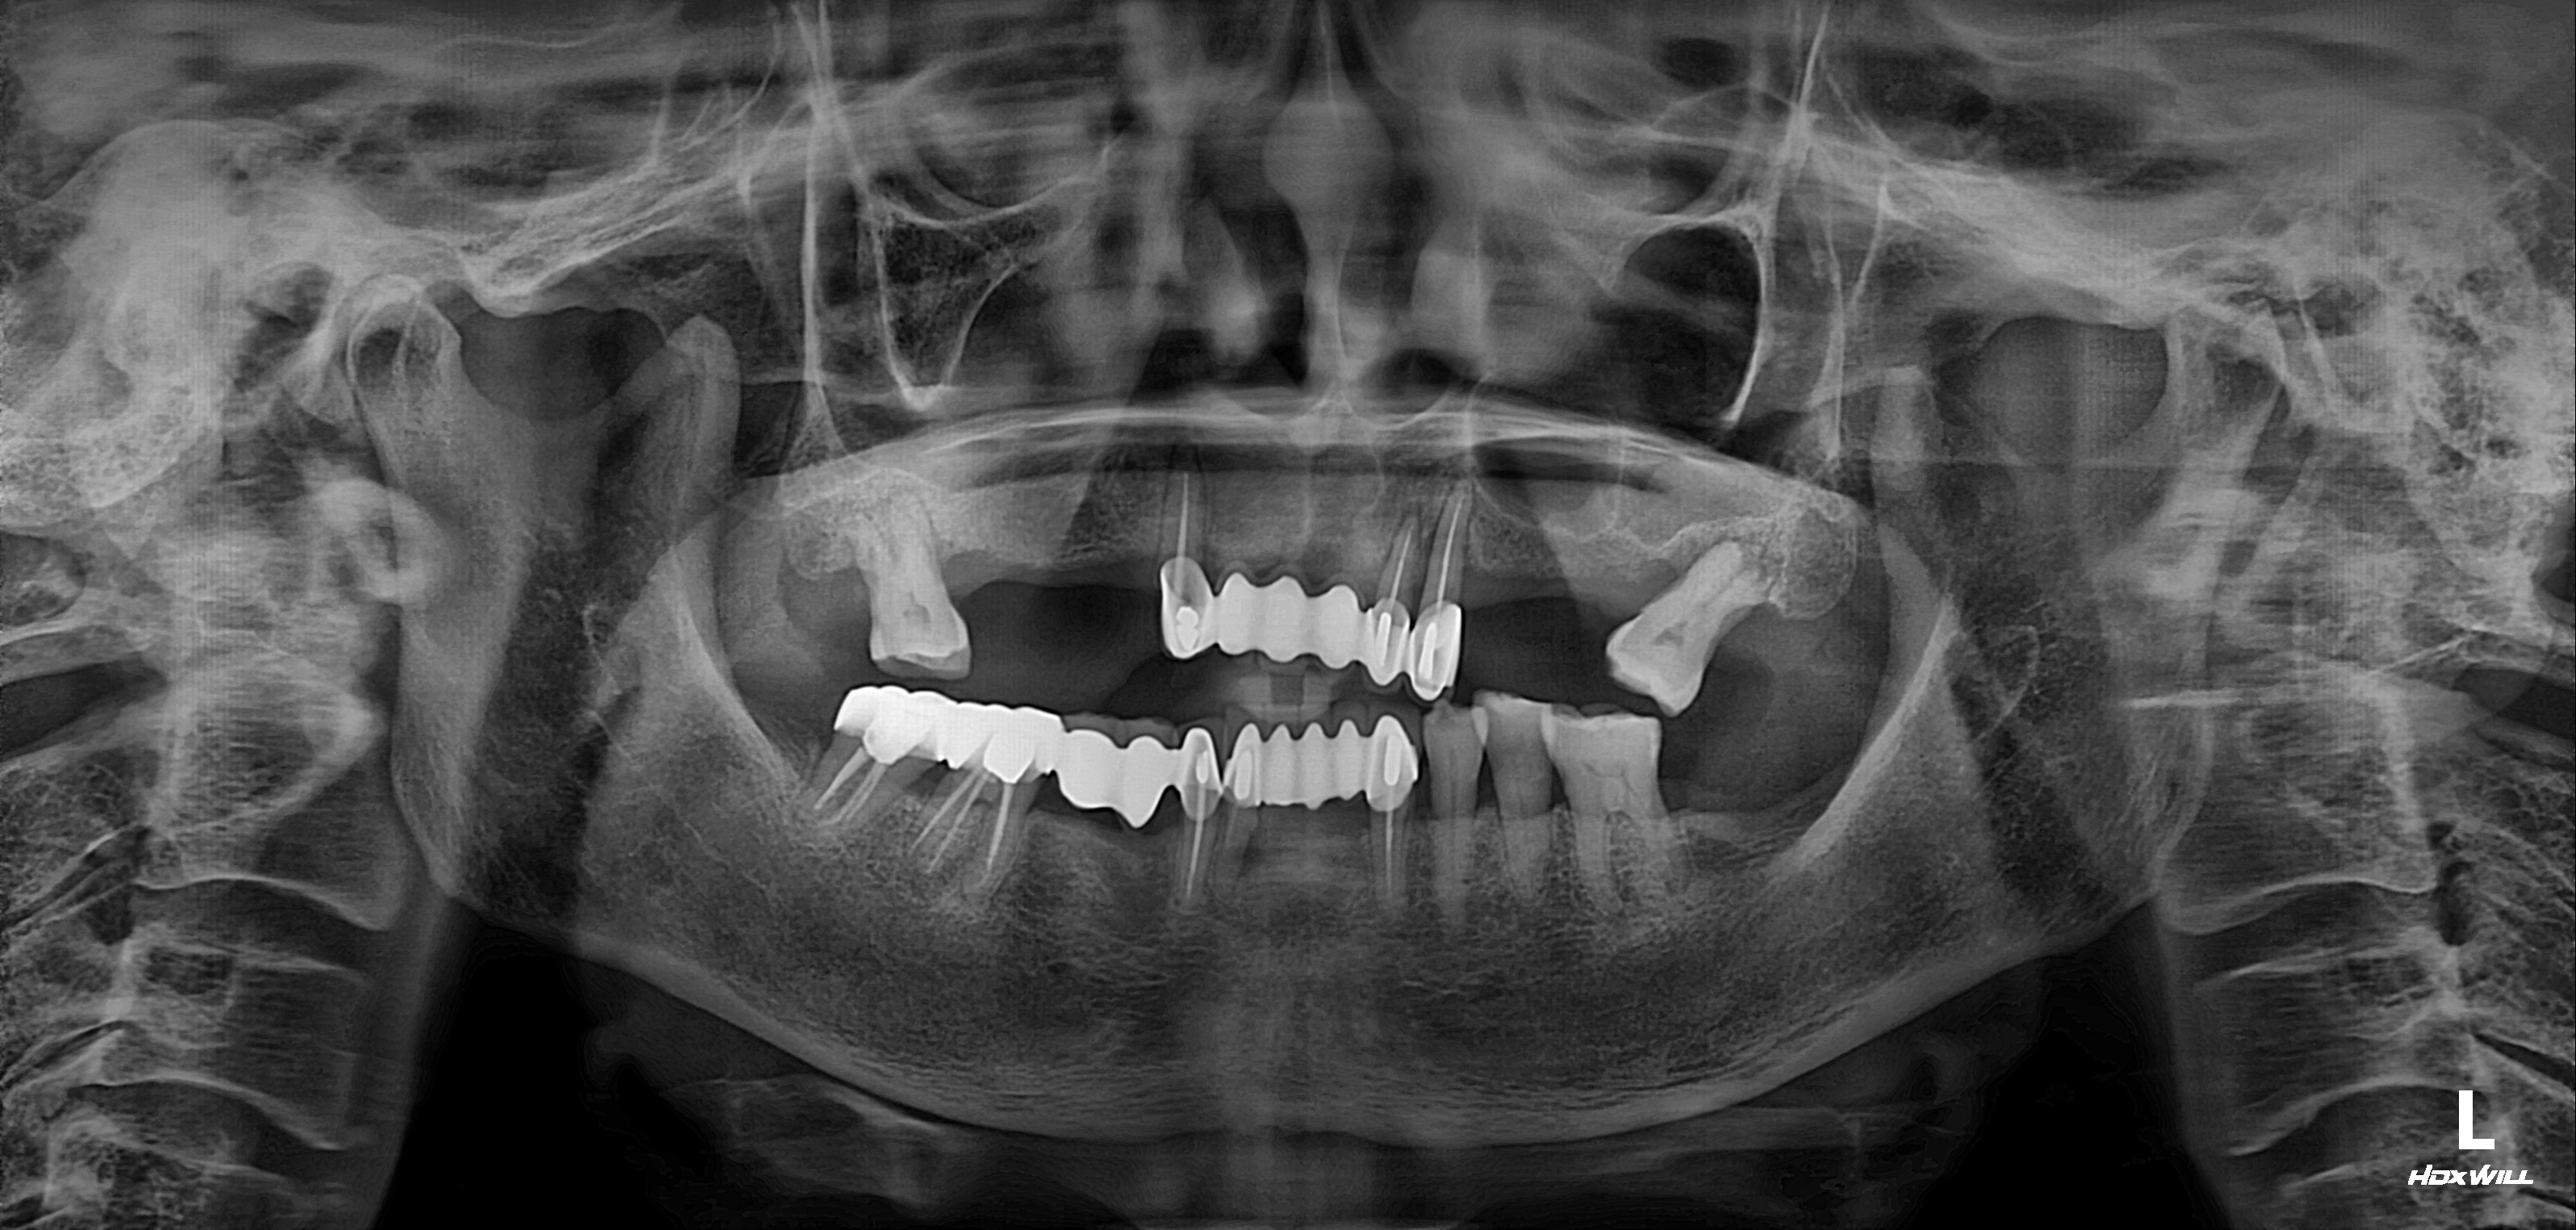

수술 전

수술 후

전악임플란트 식립사례

전후사진